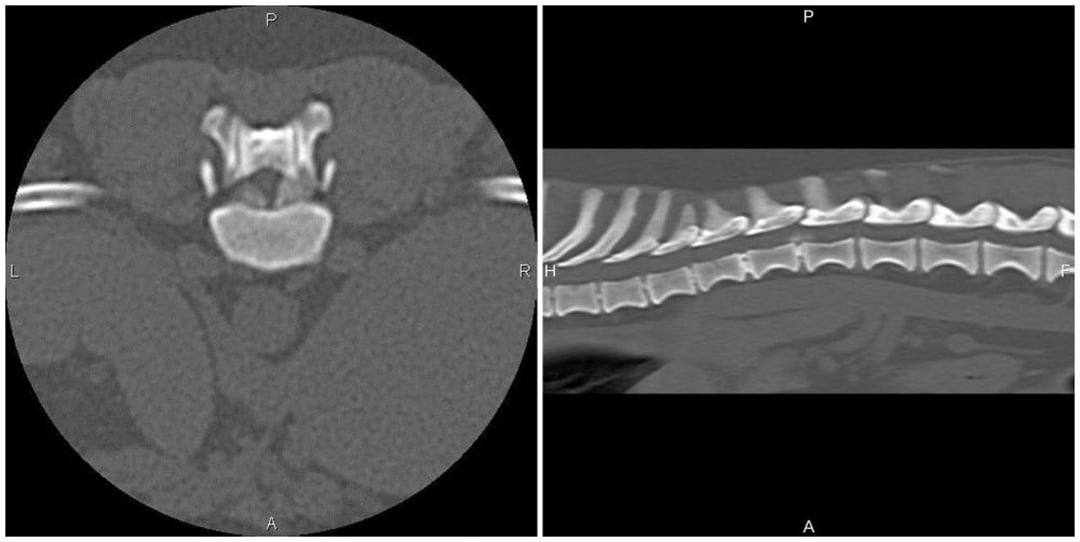

From www.merckvetmanual.com

ImageHerniated disc, CTMerck Veterinary Manual Slipped Disk Vet A gelatinous substance that is. Compressive and noncompressive manifestations of ivdd occur. There are two main types of disease that can afflict the intervertebral disk, causing it to press painfully against the spinal. Clinical presentations include cervical, thoracolumbar, and lumbosacral localizations. Canine intervertebral disk disease (ivdd) is the most commonly seen spinal disorder. Intervertebral disc rupture is generally thought to. Slipped Disk Vet.